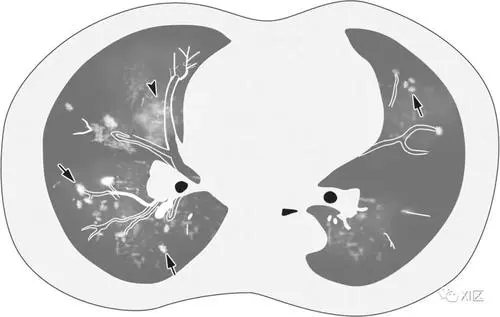

AIDS患者CMV肺炎無特異性,常合并全身CMV感染,如視網(wǎng)膜炎、結(jié)腸炎、膽管炎和食管炎。胸片和CT常見兩肺毛玻璃樣、粟粒樣或結(jié)節(jié)樣改變。血常規(guī)提示周圍白細胞的下降。

(1)胸部X線:于病初可能無異常發(fā)現(xiàn)。隨病情進展?jié)u出現(xiàn)兩側(cè)彌漫性間質(zhì)性肺炎或肺泡浸潤,常開始于肺的外周部位,累及肺底。